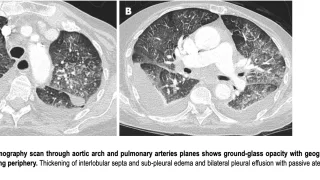

午前の病院での仕事と慢性心不全の急性増悪の患者朝, 病院に向かう途中, 空は澄み渡り, 遠くの山々が紅葉で染まって見えました. 久しぶりの秋晴れです.8時から後輩医師とともに病棟回診を開始. 昨日, 後輩が執刀した両側人工膝関節全置換術の高...